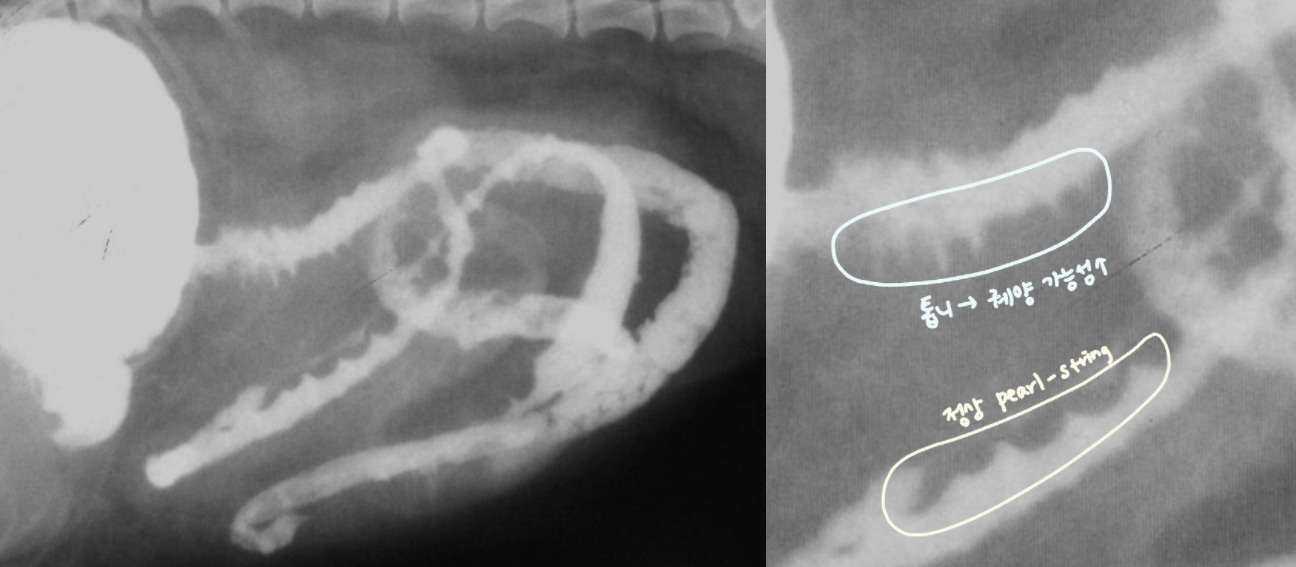

| - ์ฃผ๋ฆ๊ด ํํ์ ์๋ โ ์กฐ์์ ๊ฐ ์ผ์์ ์ผ๋ก ์ถ์ ๋์ด ์ค๋ฌด๋ฌ ๋ชจ์์ผ๋ก ๊ด์ฐฐ๋จ. |

| - ์์ฅ์ ๋ถ์ (pearl-string sign) : ๋ถ์ ์ด ๋ ์ ๋ณด์ฌ์ ์ง์ฃผ ๋ชฉ๊ฑธ์ด ๋ชจ์์ผ๋ก ๊ด์ฐฐ๋จ. |

| String sign / Accordian sign (์ ์ ์ด๋ฌผ) |

|---|

| ์ ์ ์ด๋ฌผ์ ์ํด ์ฅ(์ฃผ๋ฆ)์ด ๊ณ์ ๋ฐ๋ ค์ ๋ํ๋๋ sign. |

![]() ![]() ์ ์ ์ด๋ฌผ์ ์ฅ์ ์์ ํ ๋ง์ง ๋ชปํด fluid๊ฐ ์ ๋ฅ๋ ์ ์์. |